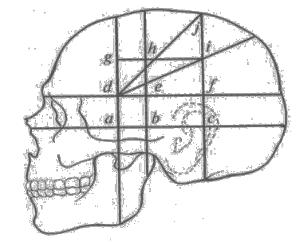

Анатомические изображения срединной сагиттальной линии черепа